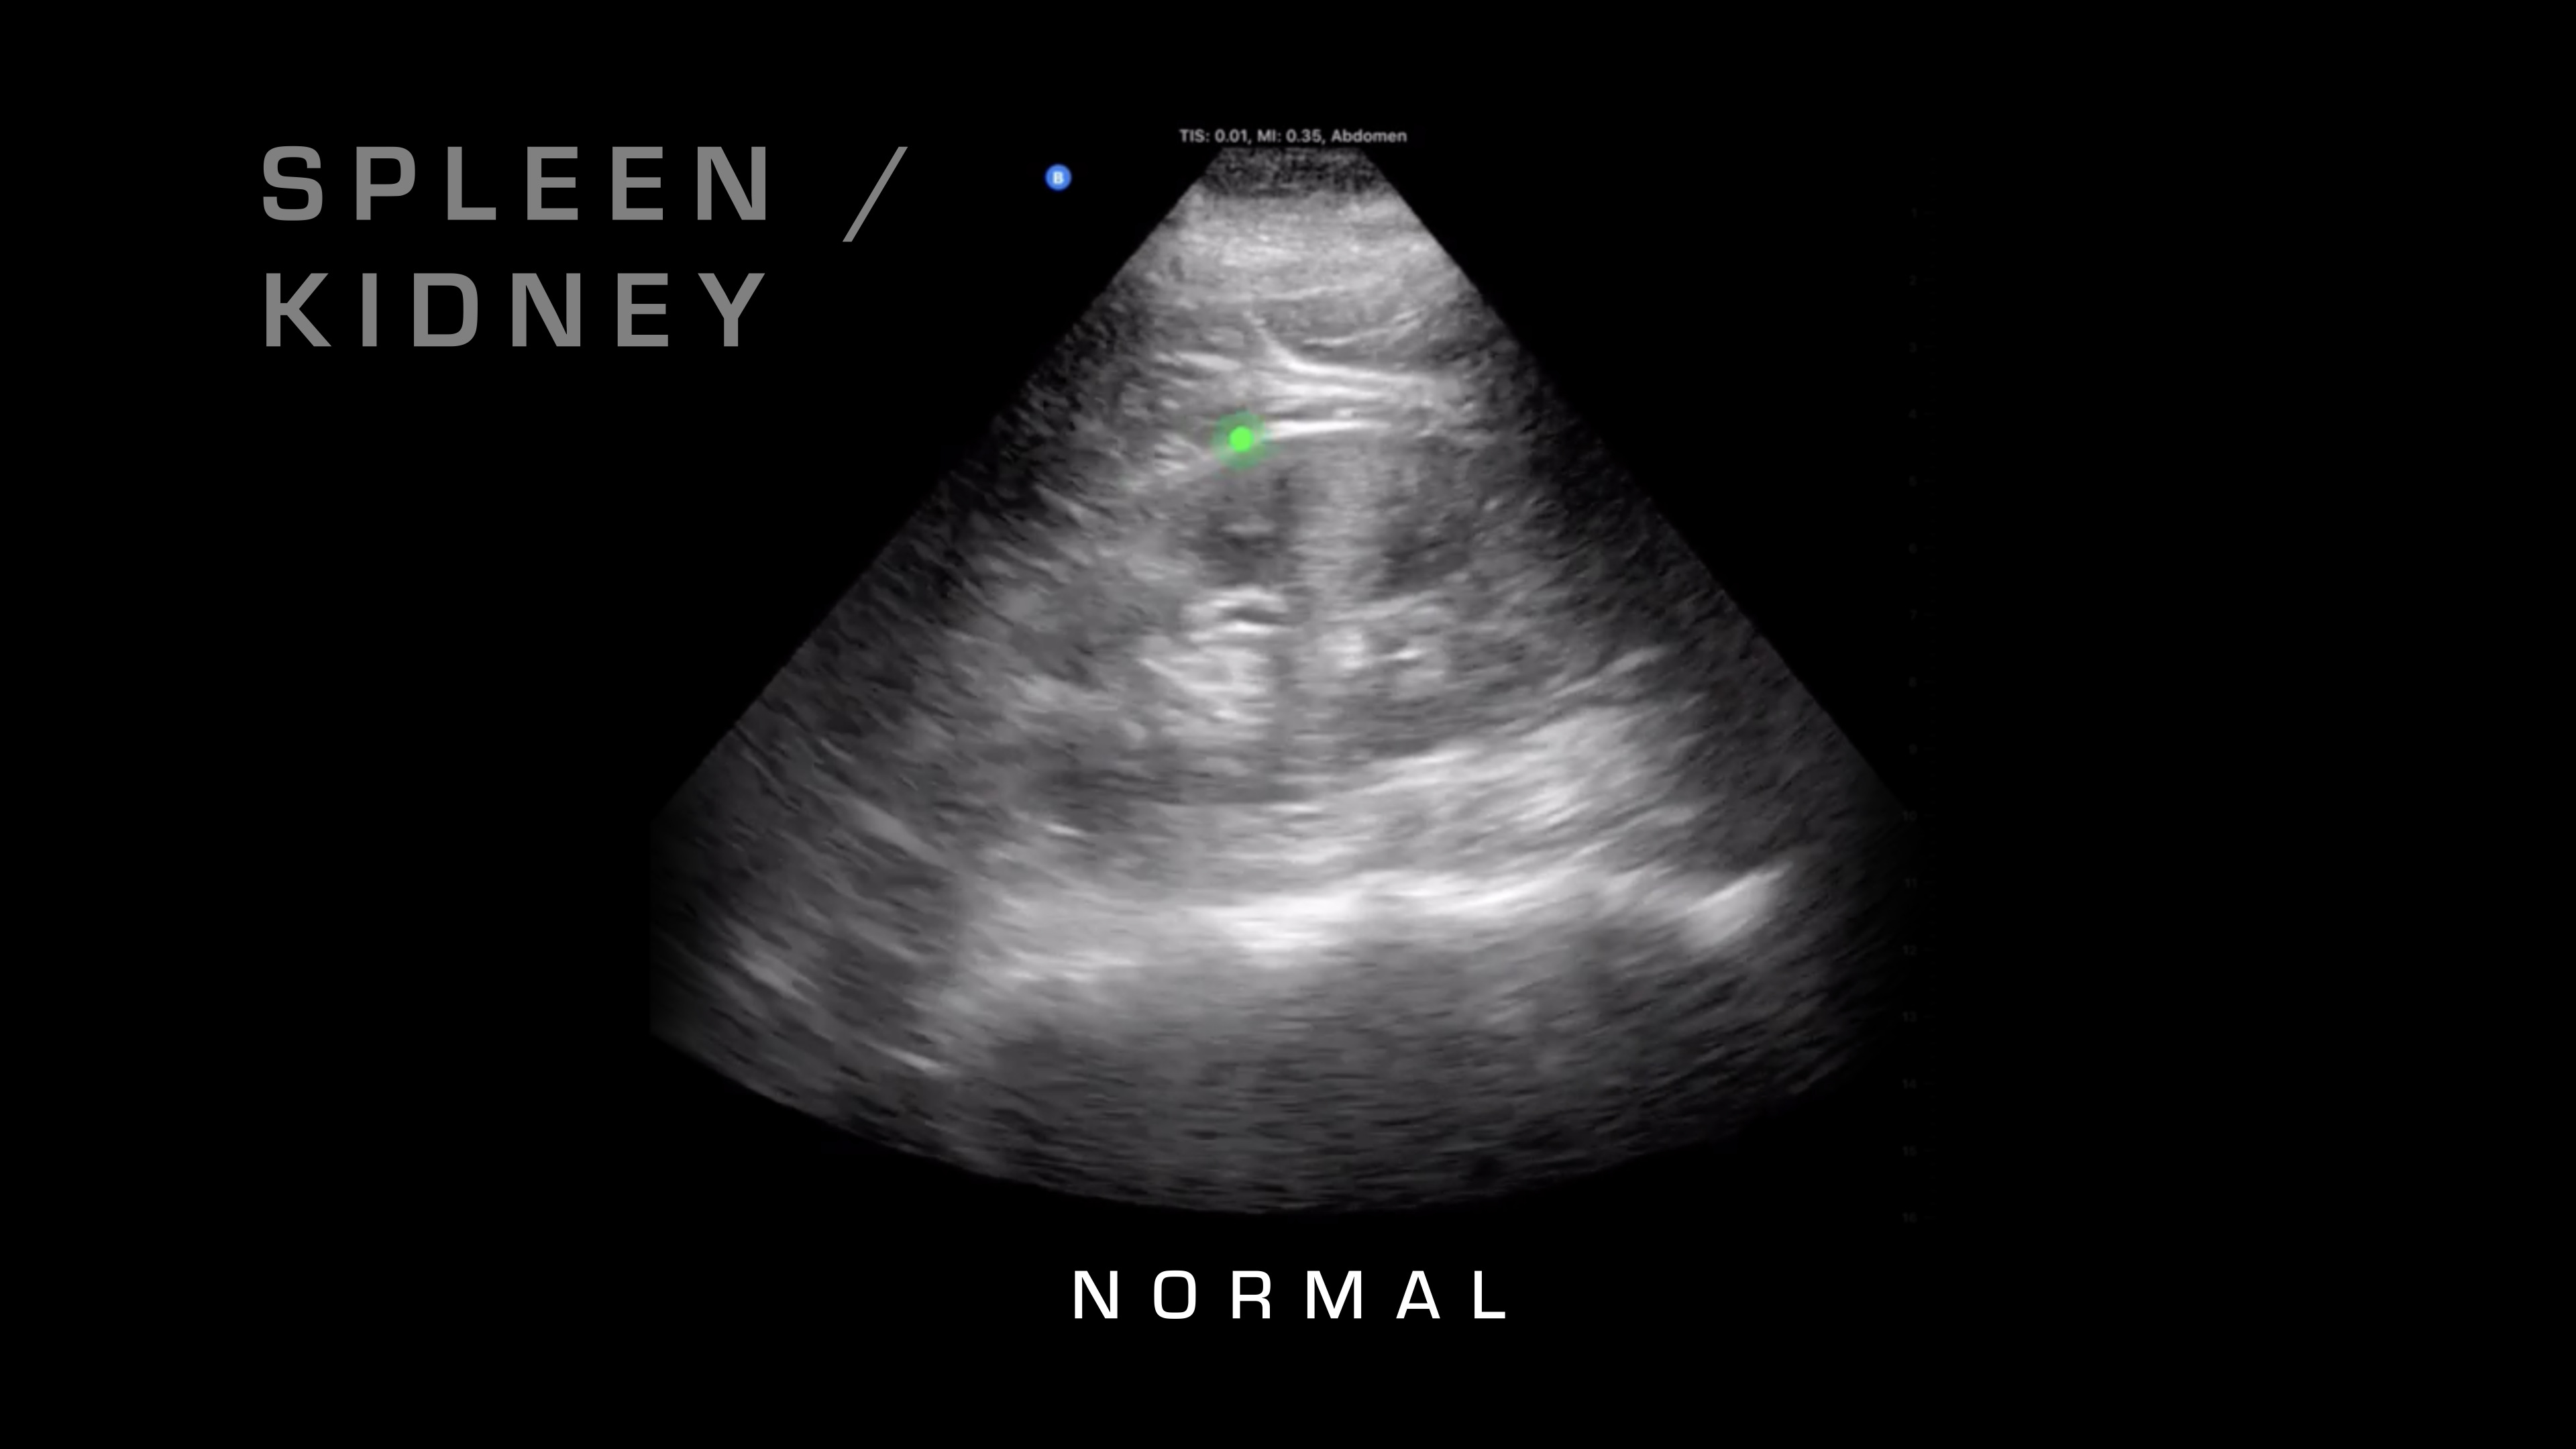

Spleen and Kidney

Then the first thing that I'm going to do is I'm going to place it down over here. What am I looking for here? I'm looking for the spleen and the kidney where they intersect. Sometimes you can tell if it's a cracked or a fractured spleen, if there's a big hematoma within the spleen, but really, we're looking for free fluid in the abdomen, which is going to be blood.

So what does blood in the abdomen look like? Blood looks like a black spot because, as the ultrasound waves penetrate through, it travels with minimal reflection, so it's just going to look like a black spot.

So I'll show you some normal, and then here's an abnormal one where you can see the fluid that's built up between the spleen and the kidney.